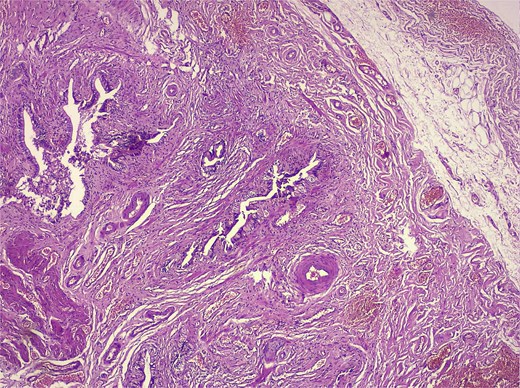

Histological analysis showed mucosal invaginations forming Rokitansky–Aschoff sinus–like diverticula surrounded by hypertrophic smooth muscle bundles, consistent with adenomyosis. The stroma exhibited lymphoplasmacytic infiltrates, hypertrophied nerve fibers, and vascular dystrophy. In deeper sections, areas of vascularized granulation tissue contained trabecular bone formation, confirming osseous metaplasia. No dysplasia or neoplastic proliferation was identified (Figs 2–4).

Low-magnification histology (H&E) low-power view demonstrating deep mucosal invaginations forming Rokitansky–Aschoff sinus–like diverticula extending into a hypertrophic muscular layer, consistent with adenomyosis. The surrounding stroma shows chronic inflammatory infiltrates without dysplasia or malignancy.